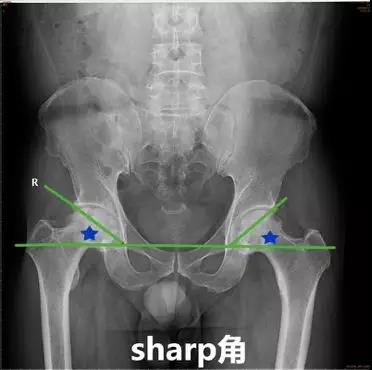

- Sharp角:即双侧泪滴下端连线与泪滴下端至髋臼上缘连线所成的角。

- 正常值:33°~38°

- 临床意义:<32°很少见且无临床意义39°~42°为正常值的上限,42°~47°需动态观察,>47°可认为异常。评价髋臼发育和髋臼对股骨头的覆盖情况。